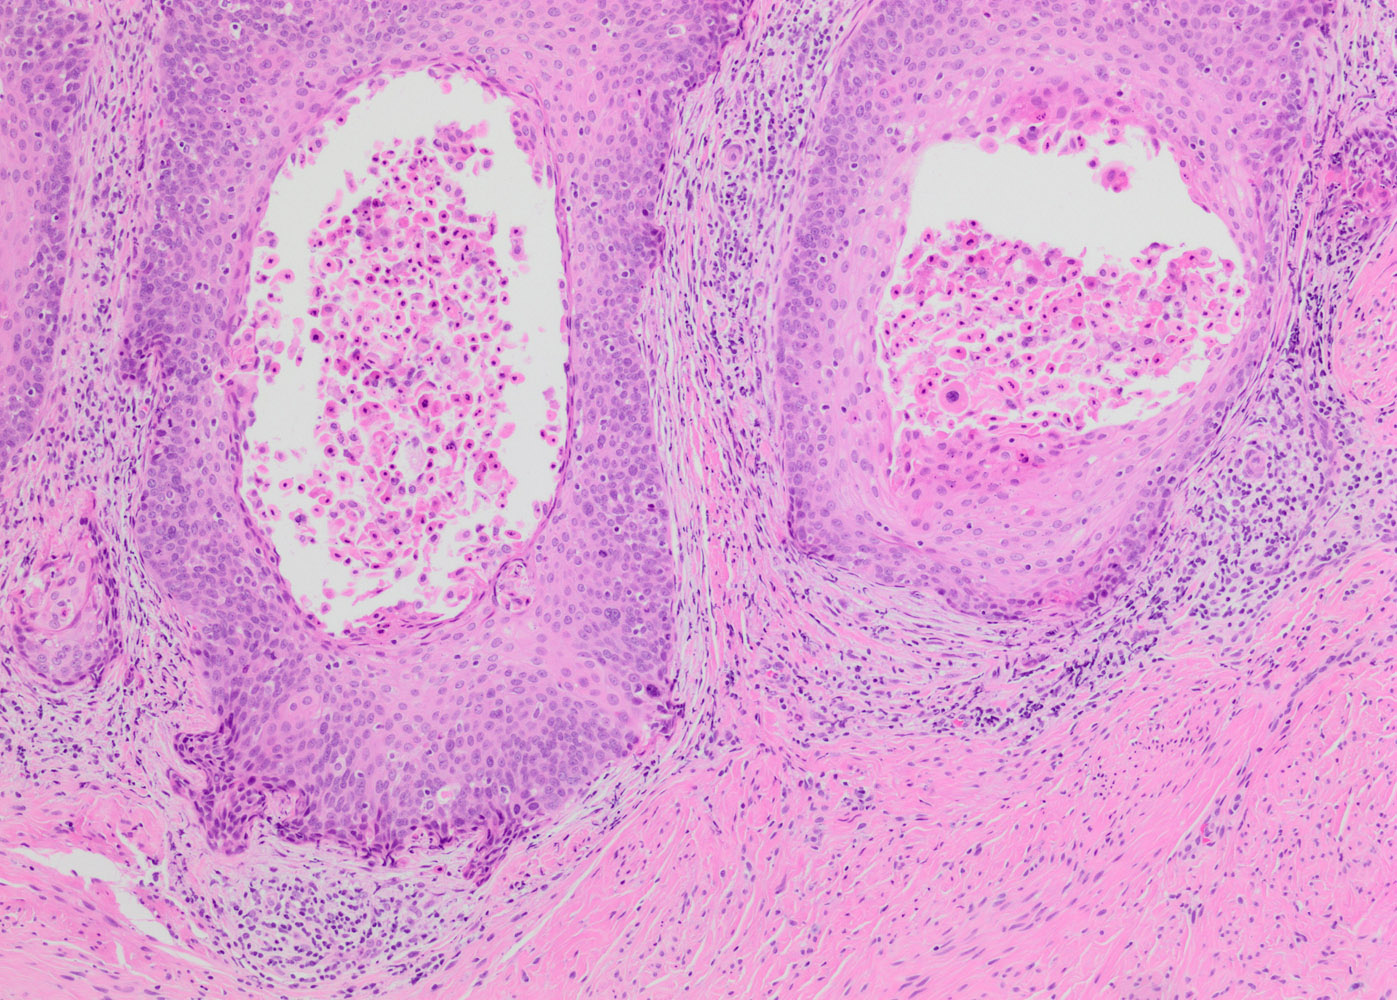

- Conventional / classic pattern: full thickness nuclear abnormalities (hyperchromasia, coarse chromatin, irregular nuclear contours and inconspicuous nucleoli), high N/C ratio in at least lower two - thirds of epithelium

- CIN III: full thickness basal / parabasal type, no maturation difference across layers

- Increased mitotic activity with atypical mitoses

Microscopic (histologic) images

Contributed by Khaled J. Alkhateeb, M.B.B.S.

- Invasive squamous cell carcinoma:

- May be difficult to distinguish from HSIL with complete replacement of endocervical glands or when dysplastic epithelium is displaced into stroma during prior surgical procedure

- HSIL involving endocervical glands shows smooth contours without desmoplastic stromal reaction or paradoxical maturation